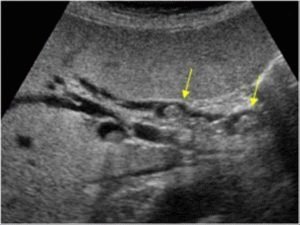

Ультразвуковое исследование — точный способ определить наличие камней. Оно позволяет не только увидеть месторасположение, но и узнать точный размер и их количество. Часто люди узнают о своей проблеме случайно. Но УЗД — не единственный метод диагностирования:

- ультразвуковое исследование брюшной полости;